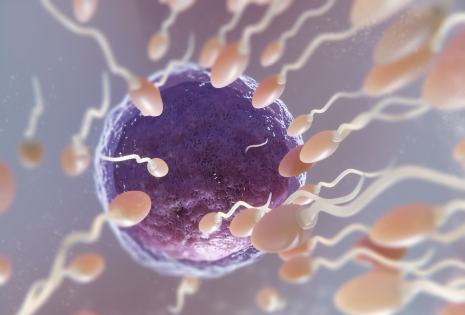

Fertility is not only “female.” We run male fertility assessments too and create a plan for the couple, not just one partner. This is why our cycles show higher success.

IVF & ICSI

A complete range of advanced fertility treatments to support successful conception.

IUI Treatment

Gentle, less-invasive fertility support for couples trying to conceive naturally.